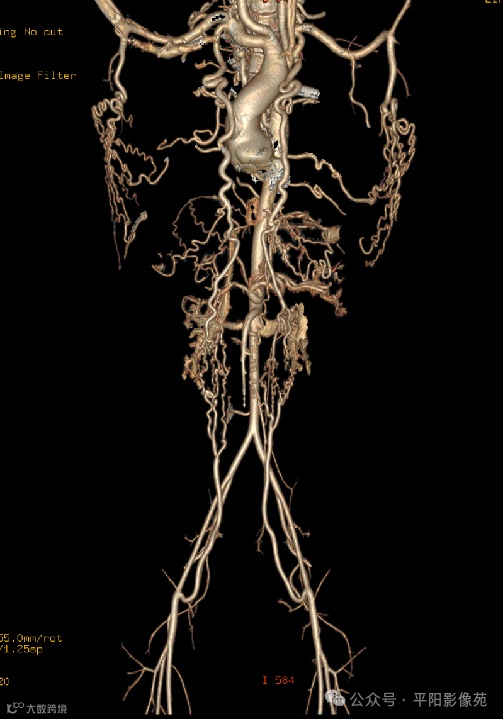

主动脉弓离断合并室间隔缺损